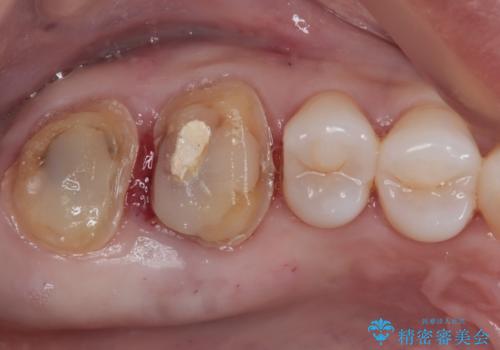

- むし歯治療途中で放置していた奥歯から、歯磨きの度に出血するとのことで来院された患者様です。

隣接する部分の間のむし歯が歯肉の奥深くにまで及んでおり、歯肉が腫れやすい状態となっていたため、歯肉の切除並びに歯槽骨の形態修正を行い、虫歯が歯肉の外に出てくるようにした上で、オールセラミックにて補綴することとしました。